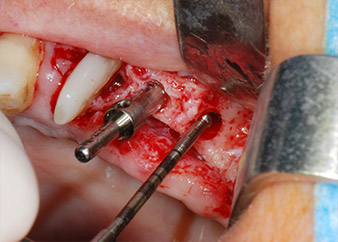

Zunächst wurde in einem Versuch, das Paro-Endo-Problem zu lösen, an der verbleibenden Wurzeloberfläche ein vorsichtiges Debridement mit einem piezochirurgischen Gerät vorgenommen (Piezomed, W&H) (Abb. 4); dann wurde der Apex mit dem gleichen Instrument im Sinne einer WSR abgetragen, um das verbleibende infizierte apikale Gewebe zu entfernen (Abb. 5). Eine retrograde Füllung war nicht notwendig, da die orthograde Füllung gerade revidiert worden war.

Vor der Insertion der Implantate wurde infiziertes Weichgewebe im Implantationsbereich und um das Abutment mit einem Instrument entfernt, das laut Hersteller primär zur Knochenbearbeitung und zum Sammeln von Knochenspänen vorgesehen ist (Piezomed, Einsatz B5) (Abb. 6 und 7).

Im folgenden Schritt wurde das jeweilige Implantatbett an den Positionen 25 und 26 mit rotierenden Instrumenten in einem Winkelstück mit einem Übersetzungsverhältnis von 20:1 (WS-75 L G, W&H) und einem vor Kurzem aktualisierten leistungsstarken Implantatmotor präpariert (Implantmed, W&H) (Abb. 8 und 19).